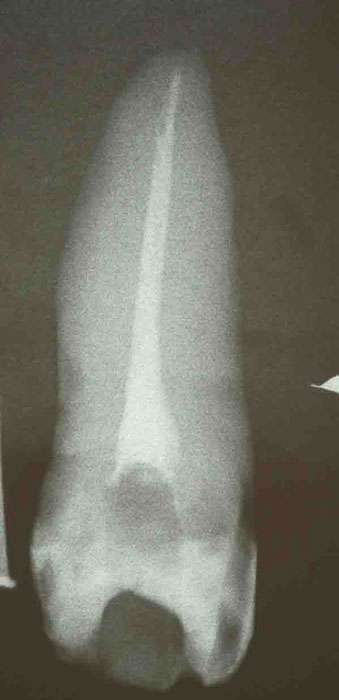

Mittlerer oberer Schneidezahn als transparentes Präparat nach in-vitro-Behandlung

Im apikalen Drittel verzweigt der Wurzelkanal in zwei separate Äste, von

denen nur einer erfasst ist. Die untypische Krümmung des Instruments in

der Messaufnahme gibt einen Hinweis auf die vorliegende Aufzweigung.